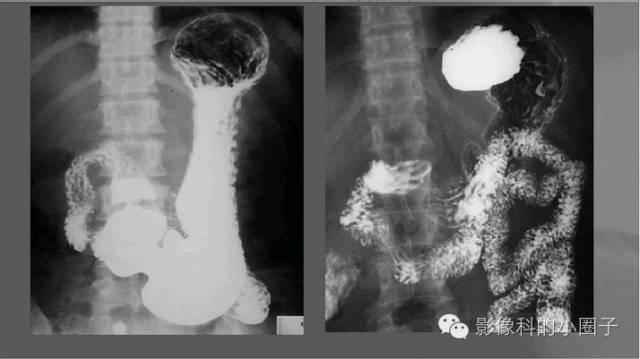

小肠造影

小肠内有什么消化器官,你了解和不了解的\

小肠包括十二指肠、空肠与回肠,起自胃幽门,终于进入盲肠的回盲部。十二指肠形似C行,全长约25 cm,相当于本人十二根手指的指幅,因此而得名。成人绝对的空回肠长度约7 m,但在正常人体内由于肠管持续肌张力的存在,小肠长度明显缩短,测量时仅约3 m。空肠的起始标志为十二指肠悬韧带。空肠约占全小肠的40%,回肠占60%,二者间常无明显解剖学标志。

十二指肠 分四段

球部:三角形,穹窿对称、光滑、整齐、粘膜皱襞纵行、平行。

降部、水平部、升部:粘膜皱襞呈羽毛状,与空肠相似。

空肠

位于左中上腹、粘膜呈羽毛状、蠕动活跃,大多呈粘膜像。

回肠

位于右中下腹和盆腔。蠕动较弱,大多呈充盈像,表现为短管状,轮廓光滑,加压时可见纵行和斜行粘膜。